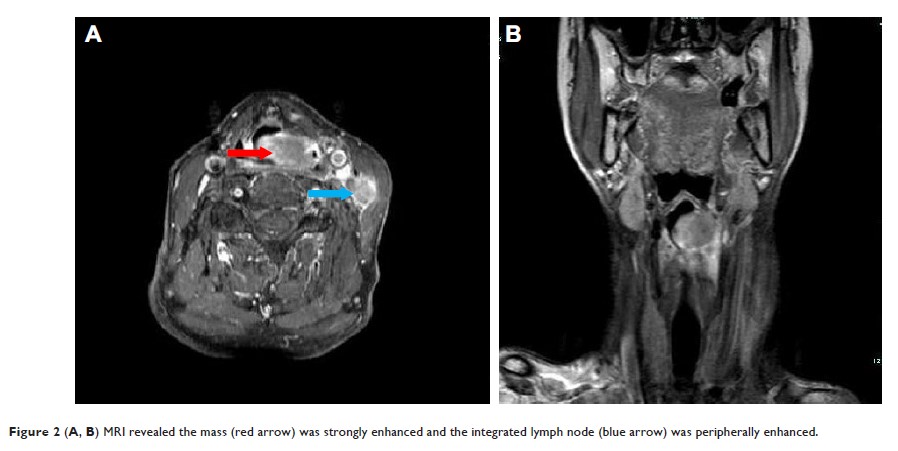

Case Report

- 作者:Yin-Jie Ao, Shui-Hong Zhou

- 期刊:OncoTargets and Therapy